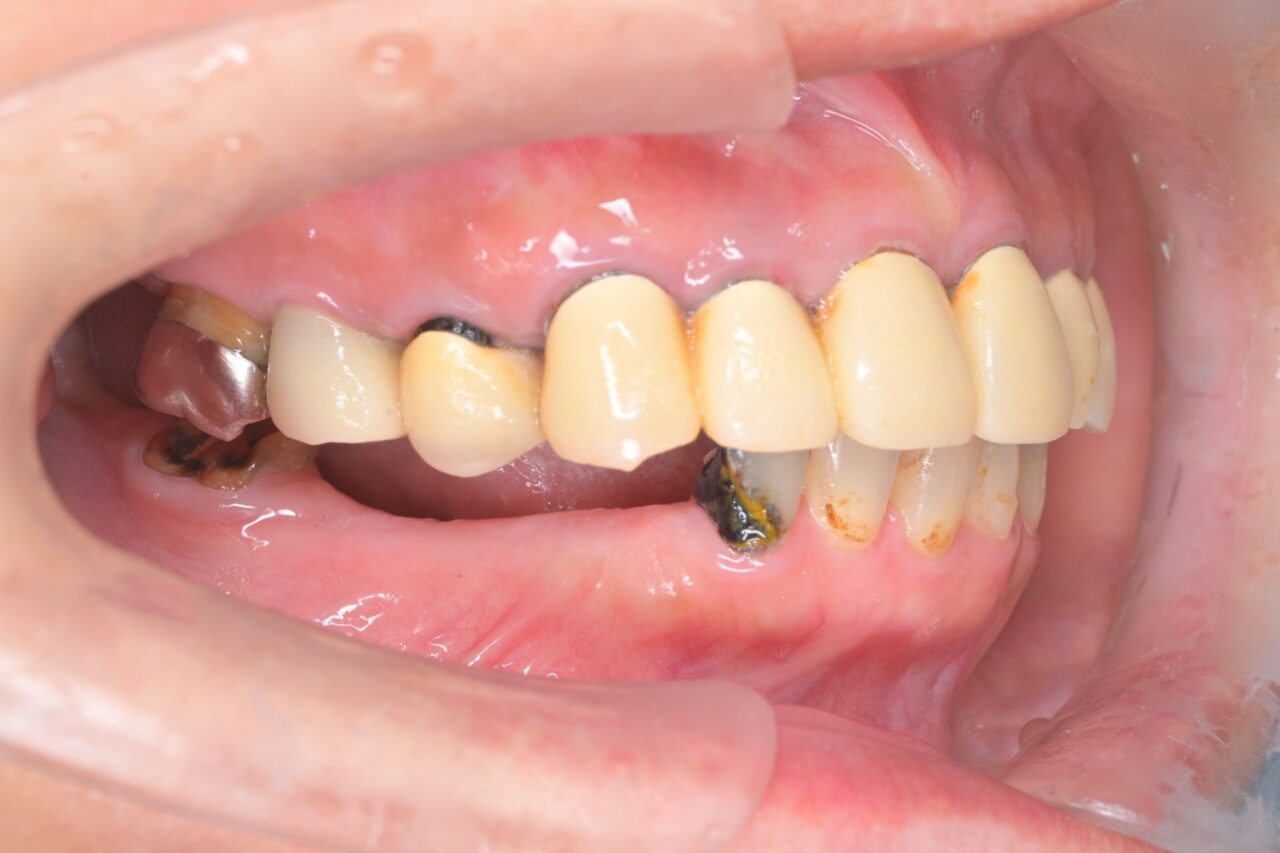

右側面

奥歯がありません。歯ぐきの際が黒くなっています。前歯があるので不格好にはならないのですが、奥歯=大黒柱が無い状態です。奥歯が無いことによって、かみ合わせが深くなってしまい、顎関節にも負担がかかっている状況です。

左側面

上下奥歯がありません(;^ω^) 虫歯が大きくなって、残根状態です。これでは、口腔内を清潔に保てないので、即抜歯です。